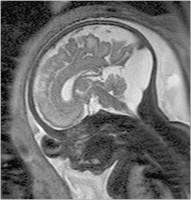

Fetus - Sagittale Schichtführung

Abbildung 1: Sagittale Schichtführung durch einen Fetus in der 27. SSW. Durch das große "Field of View" kann der ganze Fetus abgebildet werden. Das Profil, einschließlich des harten und weichen Gaumens, ist beurteilbar. Intrazerebral erkennt man kortikal den Beginn der Formation der Zentralregion, Hirnstamm und Kleinhirn. Die räumliche Auflösung ist groß genug, um kleine Strukturen wie das Chiasma opticum darzustellen. Intrauterin zeigt sich darüber hinaus eine regelrechte Nabelschnur, die – im Querschnitt getroffen – 3 Gefäße aufweist.